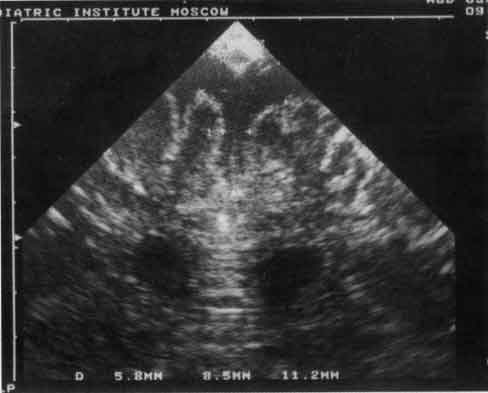

Рис. 2. Эхограмма лобных долей грудного ребенка при наружной

гидроцефалии.

Маркерами обозначены расширенные межполушарная щель и

субарахноидальное пространство.